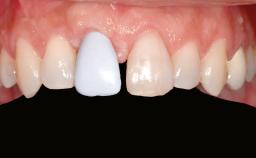

A 47-year-old Caucasian woman with a single-tooth edentulous space at the site of the left maxillary canine was referred for treatment. She had undergone traumatic extraction of this impacted canine several months before referral. Her chief complaint was the dissatisfying appearance of her smile. The patient desired a stable and esthetic rehabilitation of the site. Her dental history showed no evidence of periodontal disease or bruxism. She had no systemic diseases, was not taking any medications, and did not smoke. The extraoral examination revealed a high lip line and an inadequate soft-tissue volume at the defective canine site. Large black triangles were visible between the canine and its adjacent teeth.